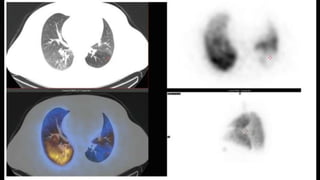

RADIONUCLIDE LUNG SCANNING

• Planar ventilation/perfusion (V/Q lung scintigraphy) scan to increase the specificity

• Tracers: Xenon-133, Krypton-81, Technetium-99

• In acute PE, ventilation is expected to be normal in hypo-perfused segments

(mismatched)

• Applied in those with a low clinical probability and normal chest X-ray particularly in

1. Female patients

2. Pregnant women

3. History of contrast medium allergy/anaphylaxis

4. Renal failure

• PIOPED study three-tier classification: normal scan (excluding PE), high-probability

scan (diagnostic of PE in most) and non-diagnostic scan

• High frequency of non-diagnostic scans is a limitation

OTHER DIAGNOSTIC MODALITIES

• SPECT (single photon emission CT ) : V/Q SPECT or preferably hybrid

SPECT/CT allows a more accurate exploration of all lung segments and better

identification of segmental and subsegmental perfusion defects typical of PE

Reduces the frequency of non-diagnostic studies

Better sensitivity and specificity than planar CTPA, needs more evidence